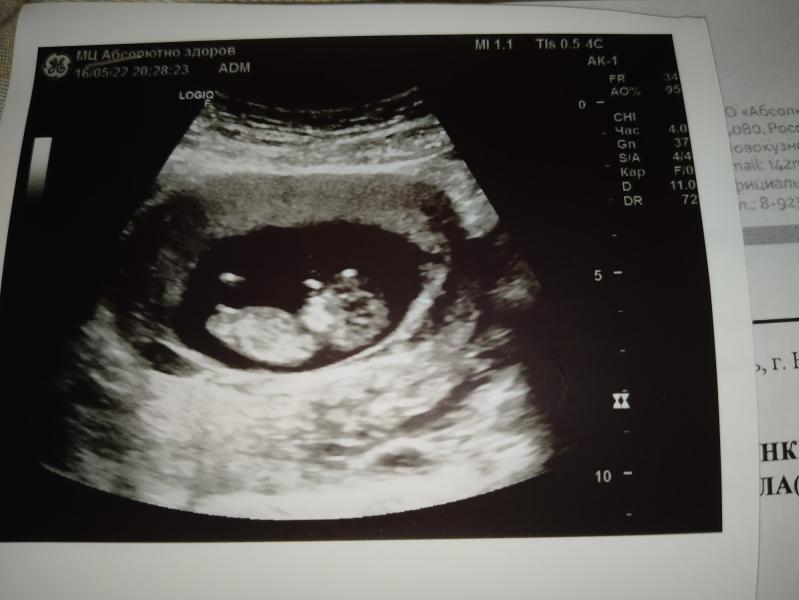

Ну вот и прошли мы первый скрининг 🤗

Впр нету, все хорошо. Предположили мальчика🥰 Но нашли амниотический тяж. Может у кого было, что это? И чем это грозит ?😕